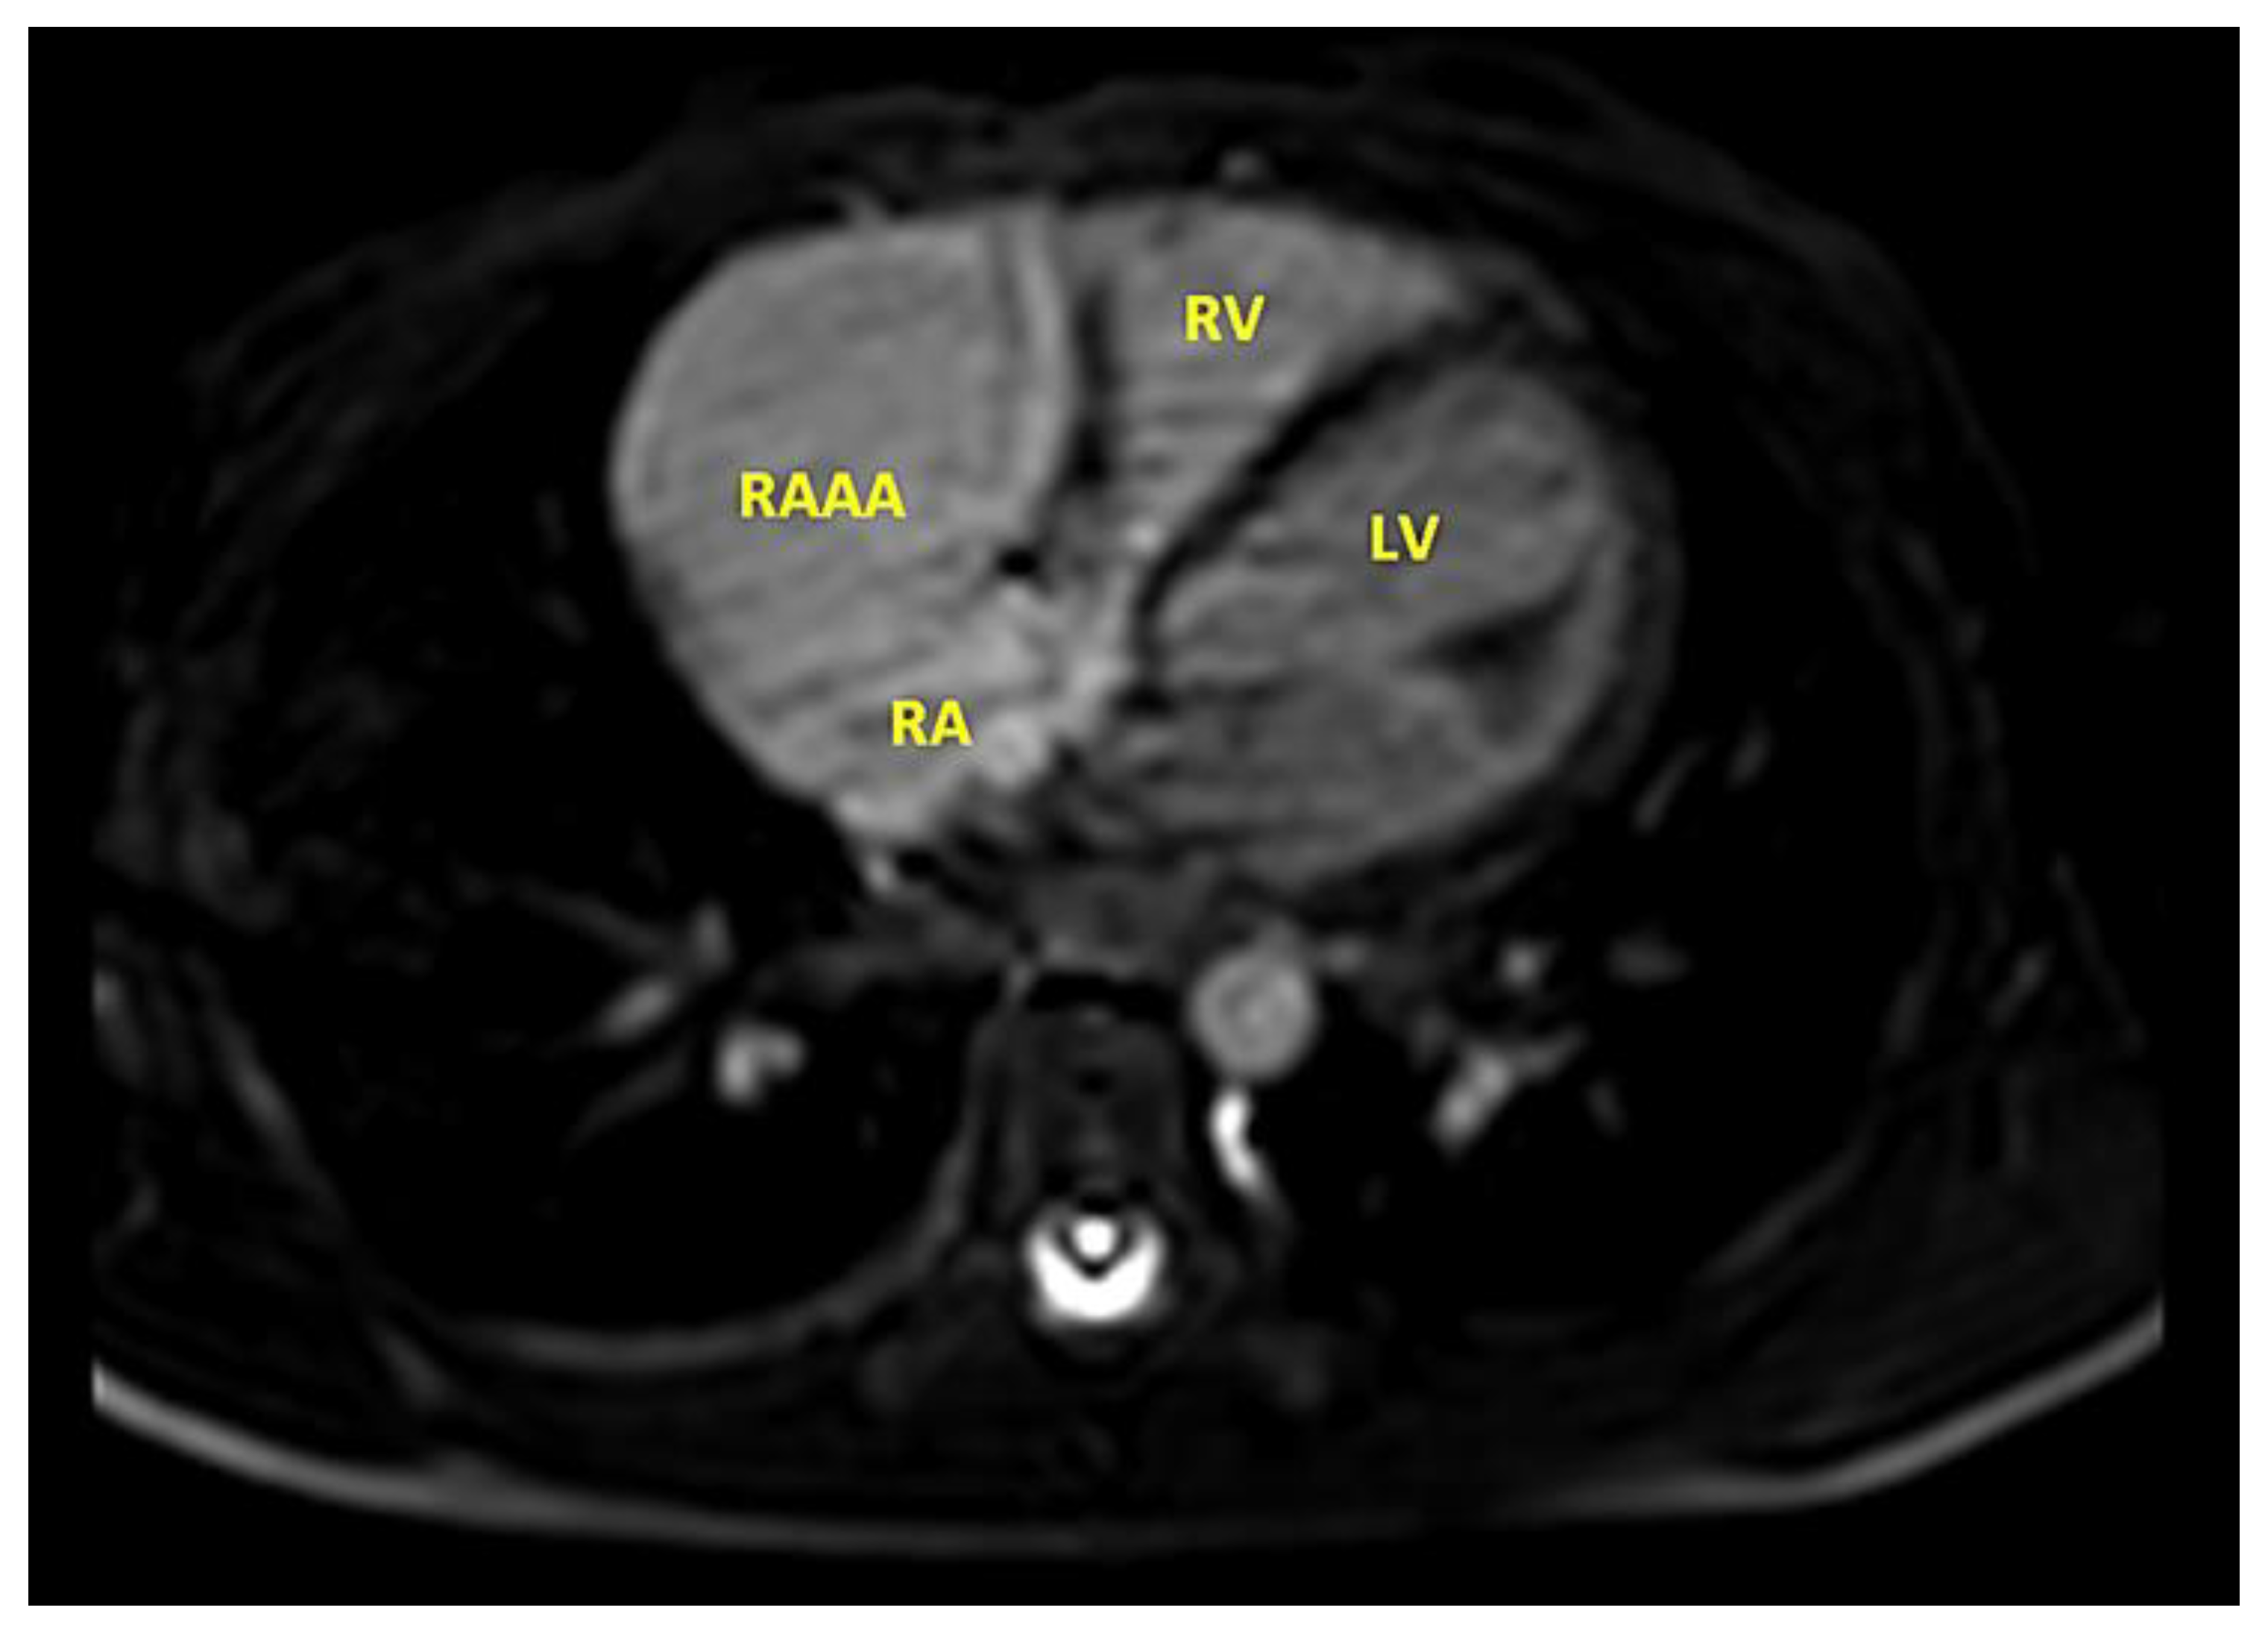

- MRI provides useful information regarding the cardiac structure, the thickness of the wall, and the route of the right coronary artery, as well as potential sites of compression.

| RAAA | Right Atrial Appendage Aneurysm |

| RAA | Right Atrial Appendage |

| RV | Right Ventricle |

| RA | Right Atrium |

| LV | Left Ventricle |

| LA | Left Atrium |